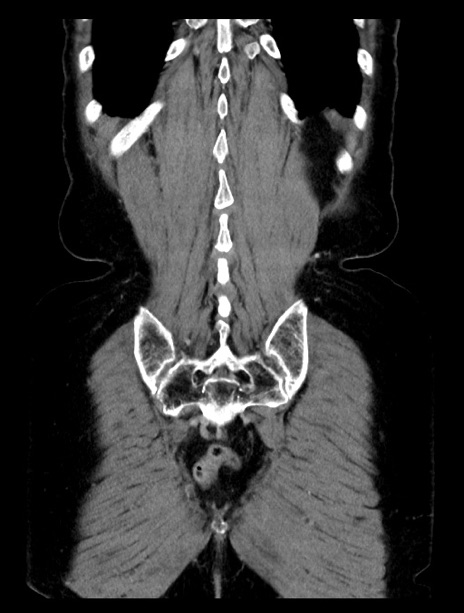

症例23(冠状断像)

【症例】70歳代女性

【主訴】下腹部痛・嘔吐

【現病歴】2日前より腹痛あり。昨日嘔吐あり。症状改善しないため来院。

【既往歴】胃GISTに対して胃部分切除後。

【身体所見】BT 37.1℃、BP 128/77mmHg、腹部:平坦・軟、下腹部に圧痛あり。

【データ】WBC 10200、CRP 0.31